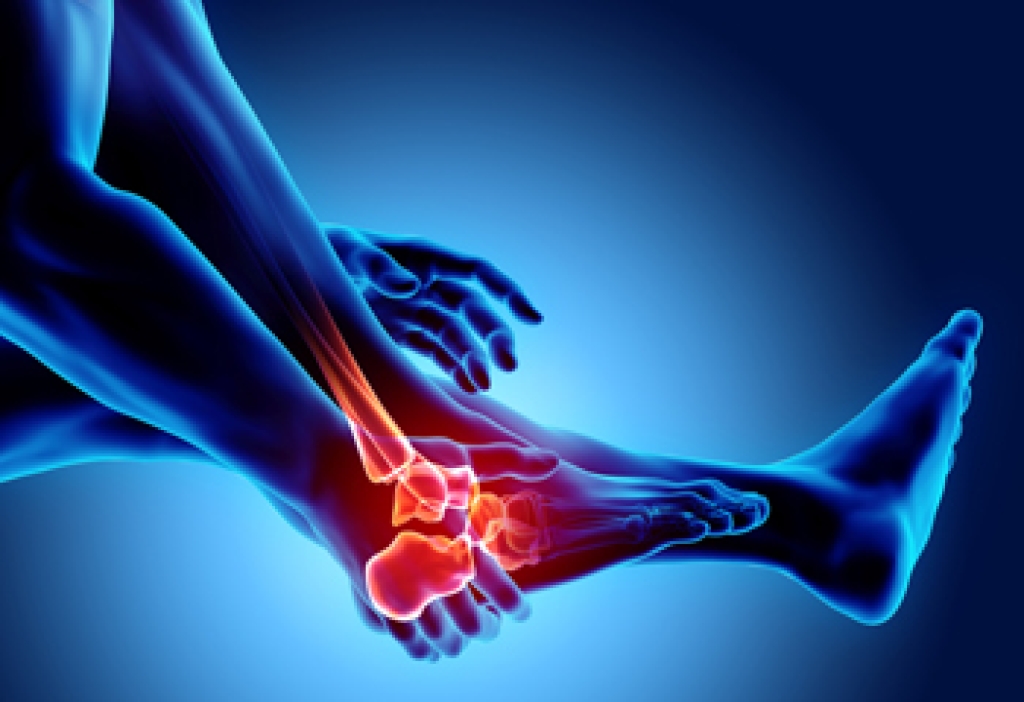

Cuboid syndrome, common among athletes and ballet dancers, occurs when the cuboid bone becomes partially dislocated due to repetitive injury, ankle sprain, or trauma. The cuboid is one of the five bones that make up the midfoot. It is important to the distribution of body weight and the stabilization of the outer midfoot. Cuboid syndrome can lead to difficulty walking. Additionally, some people experience aching pain on the outside of the foot, swelling, and increased pain when pressure is applied to the foot. One may also experience decreased motion, and ankle movement can be painful. A podiatrist’s expertise is needed for diagnosis, since so many of these symptoms mimic those of other afflictions. Treatment includes relocation of the bone, rest, and immobilization with tape, in addition to performing foot exercises for strength and flexibility. If you have troubling discomfort on the outside of the foot, it is suggested that you make an appointment with a podiatrist for a proper exam and care.

Cuboid syndrome is a common cause of lateral foot pain, which is pain on the outside of the foot. The condition may happen suddenly due to an ankle sprain, or it may develop slowly overtime from repetitive tension through the bone and surrounding structures.

Causes

The most common causes of cuboid syndrome include:

- Injury – The most common cause of this ailment is an ankle sprain.

- Repetitive Strain – Tension placed through the peroneus longus muscle from repetitive activities such as jumping and running may cause excessive traction on the bone causing it to sublux.

- Altered Foot Biomechanics – Most people suffering from cuboid subluxation have flat feet.

Symptoms

A common symptom of cuboid syndrome is pain along the outside of the foot which can be felt in the ankle and toes. This pain may create walking difficulties and may cause those with the condition to walk with a limp.

Diagnosis

Diagnosis of cuboid syndrome is often difficult, and it is often misdiagnosed. X-rays, MRIs and CT scans often fail to properly show the cuboid subluxation. Although there isn’t a specific test used to diagnose cuboid syndrome, your podiatrist will usually check if pain is felt while pressing firmly on the cuboid bone of your foot.

Treatment

Just as the range of causes varies widely, so do treatments. Some more common treatments are ice therapy, rest, exercise, taping, and orthotics.